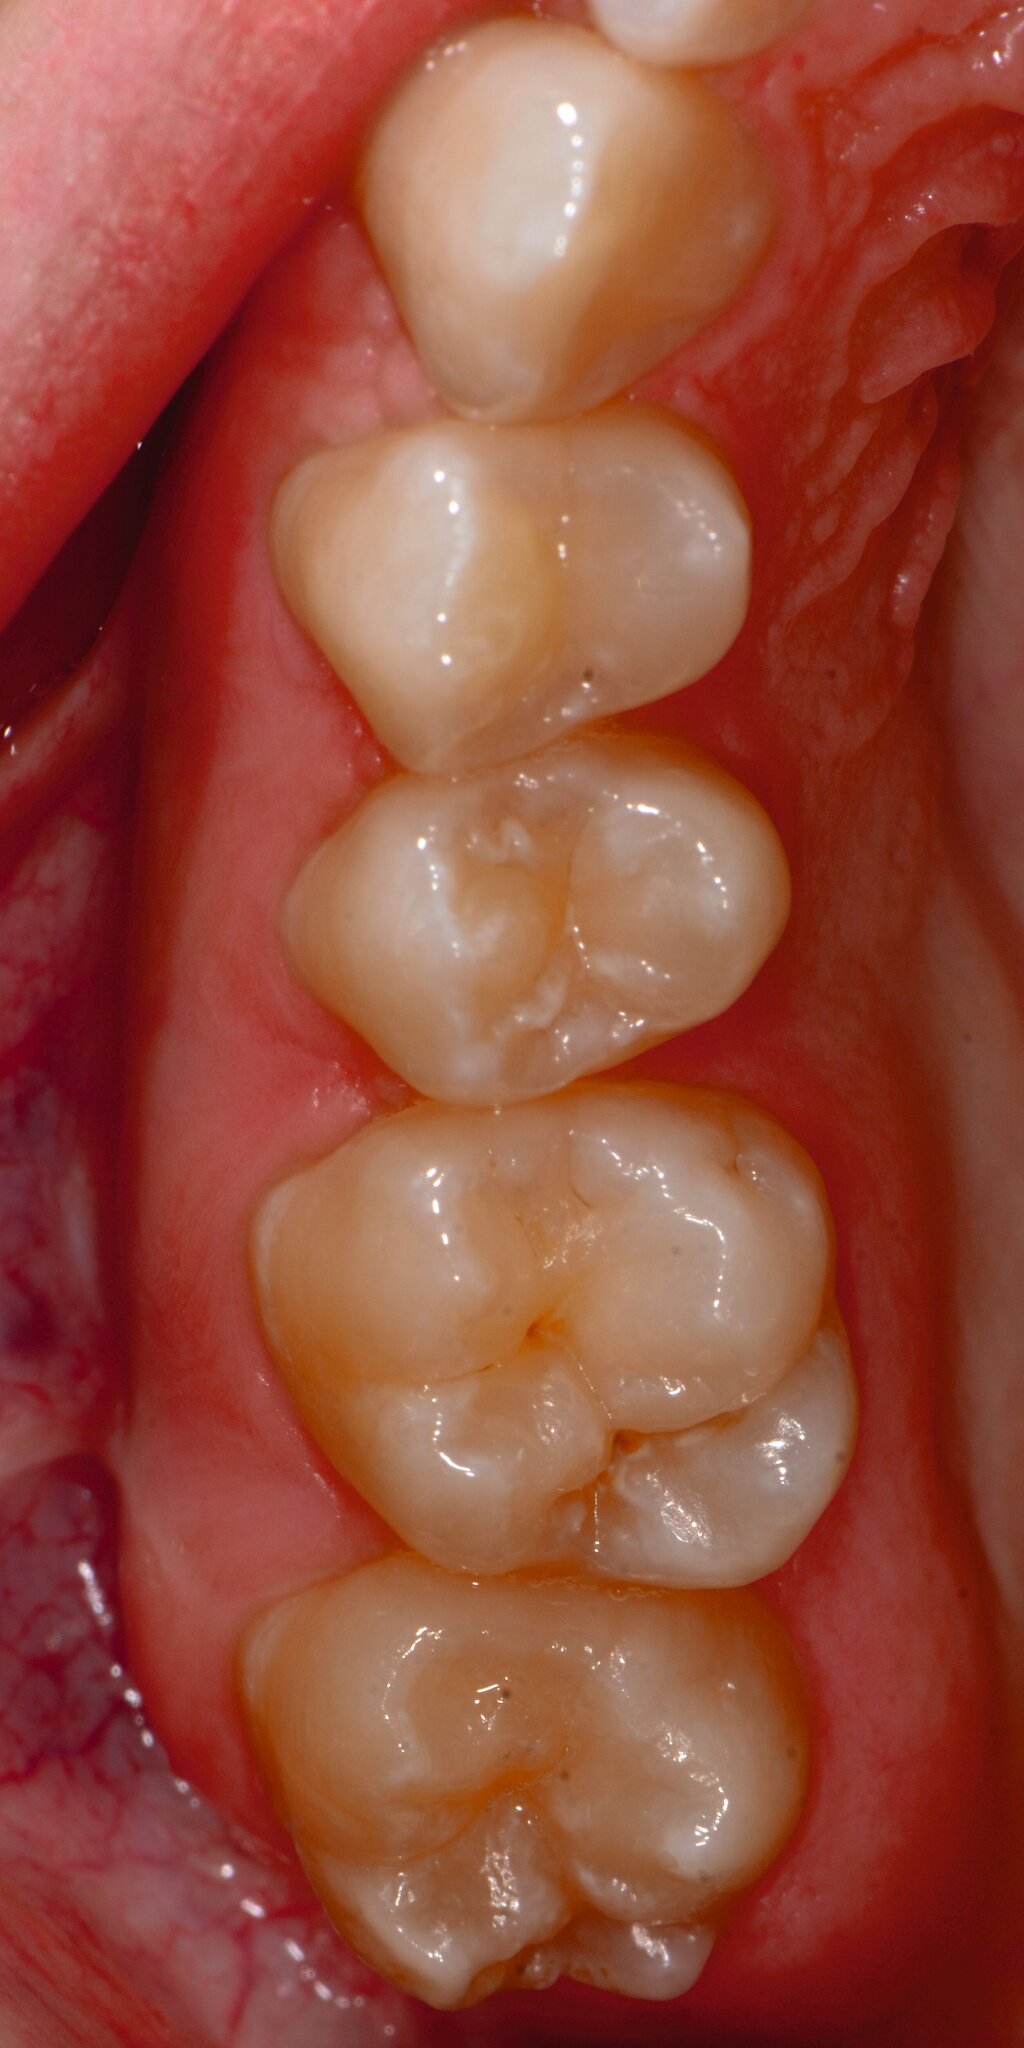

Die MIH (Abbildungen 1 und 2) stellt eine Strukturstörung der Zähne dar, die sich während der Zahnentwicklung manifestiert und daher bereits vor dem Durchbruch des Zahns in die Mundhöhle vorhanden ist. Obwohl der Name suggeriert, dass die ersten bleibenden Molaren und bleibenden Inzisiven die bevorzugten Indexzähne beziehungsweise Zahngruppen in der bleibenden Dentition sind, nutzt die Definition der European Academy of Paediatric Dentistry (EAPD) ausschließlich die ersten bleibenden Molaren zur Diagnosestellung. Entsprechend dieser Vorgabe muss zumindest ein erster bleibender Molar Zeichen einer MIH-bedingten Strukturstörung aufweisen [Lygidakis et al., 2010, 2022], damit die Diagnose einer MIH gestellt werden kann.

Das klinische Erscheinungsbild an bleibenden Zähnen zeigt typischerweise weißlich-gelbe bis gelblich-braune Opazitäten, die zumindest in einigen Bereichen durch eine scharfe Abgrenzung (engl.:„demarcated opacities“) zum gesunden Zahnschmelz charakterisiert sind (Abbildungen 3 und 4). Die abgegrenzten Hypomineralisationen befinden sich mehrheitlich im Bereich der inzisalen Kronenhälfte unabhängig von dem Auftreten an Front- oder Seitenzähnen. Die Ausprägung am Zahn kann dabei auf einzelne Areale oder Höcker begrenzt sein.

Bei einer schwerwiegenderen Ausprägung sind Zahnflächen vollständig betroffen, mitunter alle Zahnflächen an einem Zahn. Die Verteilung in der Dentition beziehungsweise an den Indexzähnen ist gleichermaßen variabel und betrifft nicht nur die Defektgröße, sondern auch die Farbe und Festigkeit. Was die Festigkeit betrifft, gilt als die Faustregel: Je dunkler die Farbe des Schmelzes, umso weicher beziehungsweise poröser und damit minderwertiger wird dessen Qualität sein. Damit reduziert sich seine kaufunktionelle Belastungsfähigkeit, was insbesondere an ersten bleibenden Molaren von klinischer Relevanz ist.

An umfangreich hypomineralisierten Zähnen können Schmelzeinbrüche (engl.: „enamel breakdown“ oder „enamel desintegration“, Abbildung 5) auftreten [Lygidakis et al., 2010; 2022]. Da diese oftmals die Folge einer fehlenden Belastungsfähigkeit des Zahnschmelzes sind und erst nach der Einstellung der Zähne in die Okklusion auftreten, werden sie auch als posteruptive Schmelzeinbrüche bezeichnet. Sie sind häufig im Bereich der Kauflächen beziehungsweise Höcker der Molaren zu finden, führen zur Dentinexposition und damit einhergehend zu ausgeprägten Hypersensitiven insbesondere bei Kindern, deren Zähne gerade erst durchgebrochen sind [Linner et al., 2021].

Für die Dokumentation und Klassifikation der MIH wurden verschiedene Systeme vorgeschlagen. Als historisch und veraltet gilt der (modifizierte) DDE-Index. Demgegenüber haben die Kriterien der EAPD – abgegrenzte Opazitäten (Abbildung 3 und 4), Schmelzeinbrüche (Abbildung 5), atypische Restaurationen (Abbildung 6) – mittlerweile die weiteste Verbreitung gefunden. Diese wurden 2003 erstmals zur Beschreibung der MIH auf empirischer Basis publiziert [Weerheijm et al., 2003] und den Jahren 2010 und 2022 im Rahmen der damaligen MIH-Workshops bestätigt [Lygidakis et al., 2010; 2022].